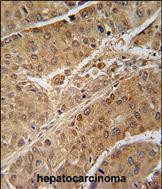

IHC 1/100-1/500 Human,Mouse,Rat

- 摘要:研究利用RPS6KB2抗体进行免疫组化,发现该蛋白在肝癌组织中高表达,并通过mTOR通路促进肿瘤侵袭和转移。